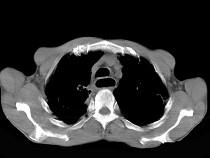

问题 女性患者,67岁,进行性吞咽困难半年,X线及CT检查如图,应诊断为()

选项 A.食道癌 B.食道憩室 C.食道炎 D.食道良性狭窄 E.食道静脉曲张

答案 A